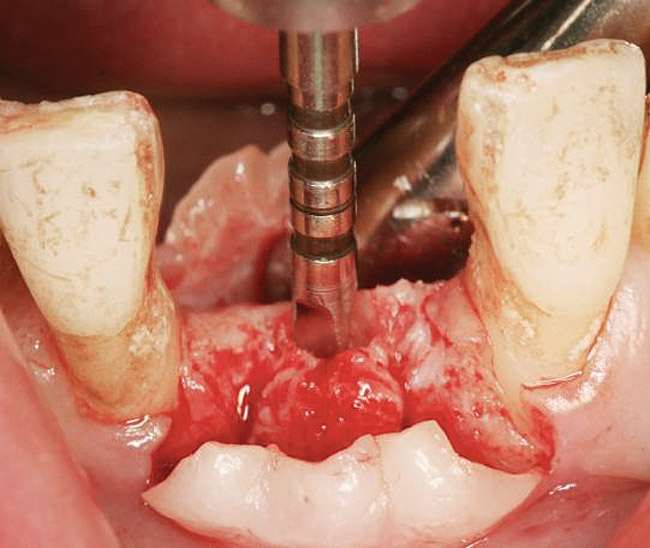

A round bur is usually used to mark the position where a 2-mm twist drill will be applied (Figure 1). Then the twist drill is employed to penetrate the cortical and trabecular bone (Figure 2). This provides information with respect to cortical bone thickness and medullary trabecular bone density. The amount of bone debris found on the twist drill can be interpreted as an indicator of bone quality (eg, the less debris and a more bloody appearance means softer bone). Four types of mineralized bone have been described by Misch (Table 1):1,2

Osteotome Sinus Elevation

Initially, a 2-mm twist drill can be employed to come within 1 mm of the subantral floor (Figure 10).32,33 Usually, if the twist drill comes too close to the sinus floor, it provides tactile feedback that the cortical bone under the sinus has been reached. Subsequently, the osteotomy can be enlarged with burs and completed with an osteotome; or after the 2-mm twist drill is used, sequentially larger osteotomes can be employed for the rest of the sinus elevation procedure.32